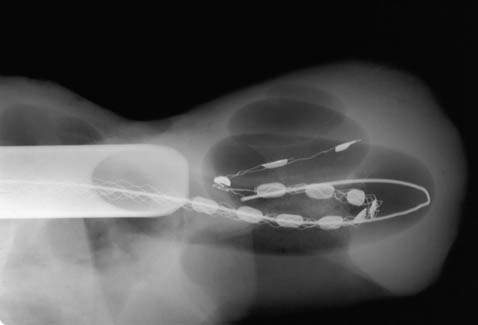

implant ślimakowy

Kliknij aby obejrzeć prezentację o umieszczaniu elektrod wewnątrz ślimaka [5,75MB]

Prezentacja przedstawiająca umieszczanie elektrod wewnątrz ślimaka ( ściągnij [5,75MB] )